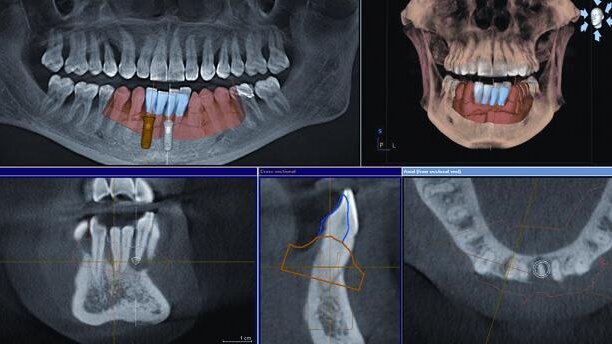

In this case report, I shall show how CBCT coupled with chairside diagnostic imaging can help in planning, simplifying and executing implant placement in the anterior mandible.

CBCT

It was decided to take a full-volume CBCT scan to further assess the upper teeth and tooth #14 for future implant replacement. The CBCT scan showed excessive bone loss around the anterior incisors with a small area of periapical radiolucency around tooth #31. A cross-sectional view showed thick, well-developed cortical plates with very little lingual concavity. Owing to the good bone height and minimal pathology, immediate implant placement was planned.

To aid implant placement in the correct angulation, a CEREC Bluecam image was taken and manipulated so that the lower tooth positions were in harmony with the rest of the dentition. This proposal was then overlaid onto the CBCT scan and was used to facilitate implant planning. The aim was to provide the patient with a screw-retained bridge with access holes though the lingual aspects of the lower incisors, whilst maintaining a sound margin of safety from the lingual cortical plate. Owing to the patient’s previous periodontal history, it was decided to use Standard Plus implants (Straumann) in this case. The design of this implant incorporates a 1.8 mm polished collar above the active surface of the implant. This results in the implant-to-abutment junction being located 1.8 mm superiorly to the bone crest.